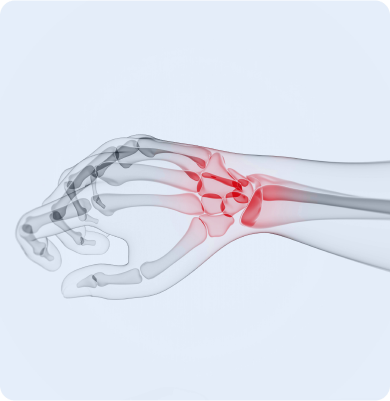

손목터널증후군

손목의 신경이 압박을 받아 발생하는 질환

주요원인

반복적인 손목 움직임이나 과도한 압박, 장시간의 손목 사용 등이 주요 원인으로 특히 컴퓨터 작업이나 스마트폰 사용 등에서 발생할 수 있습니다.

주요증상

• 손목이나 손끝에 저림이나 쑤시는 통증이 나타납니다.

• 손의 감각이 둔해지고 물건을 쥐기 어려운 증상이 발생합니다.

• 손목이나 손의 약화가 느껴지며 일상적인 작업을 하는 데 불편함을 겪을 수 있습니다.